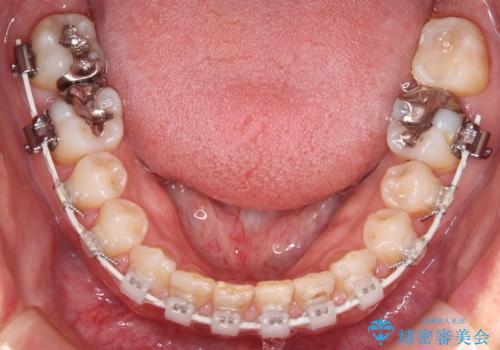

- 矯正装置

- 審美装置

- 前歯のすきっ歯が気になるということで来院されました。今回は抜歯はしないためワイヤー矯正かインビザライン矯正のどちらでも治療可能でしたが、患者さまのご希望により表のワイヤー装置にて治療をおこないました。

前歯に隙間がいくつかあったため、今回は上下でゴムかけを行いスペースを埋めるための力をかけて閉じました。もう少し早く終了する予定でしたが、ブラッシング不良による歯肉腫脹があり、一部スペースクローズに時間がかかりました。